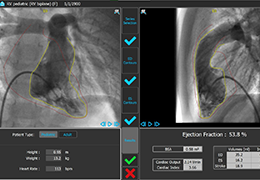

ANYTHINK 经导管主动脉瓣膜置换术分析系统